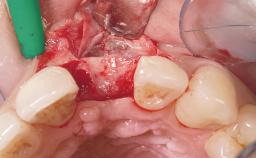

A 42-year-old female patient was referred to our clinic at the School of Dentistry of the University of São Paulo in November 2004, presenting a deficient restoration in the upper left central incisor. The clinical examination revealed no gingival retraction or any signs of gingival inflammation and, therefore, previous periodontal treatment was not considered. The patient presented a high lip line at full smile and a thin tissue biotype. This combination characterized a high-risk situation from an anatomic point of view, which required careful preoperative planning and cautious surgical execution.

Soft Tissue Grafting None

Abutment Type Customized

Prosthesis Type FDP